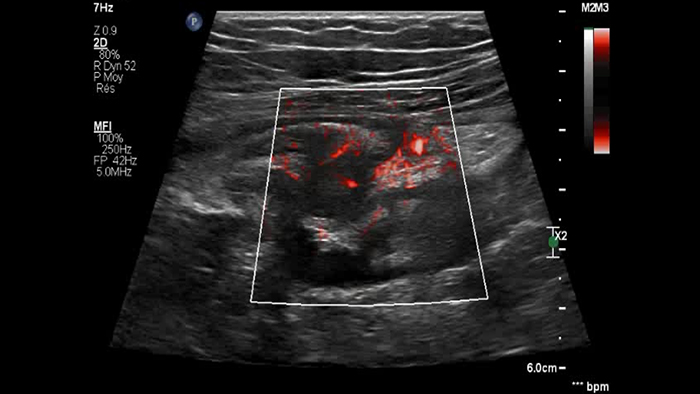

Ces images précises des lésions des couches pariétales forment la base de l’interprétation des changements induits par l’inflammation des parois intestinales et par conséquent de la différenciation entre la maladie de Crohn et la rectocolite hémorragique. L’exploration avec la technologie MFI (MicroFlow Imaging) constitue la deuxième étape. Il s’agit de reconnaître l’aspect de l’hypervascularisation induite par des épisodes inflammatoires actifs. La paroi intestinale normale semble comporter peu de microvaisseaux détectables, uniquement à l’interface de la muqueuse et de la sous-muqueuse, et dans le tissu adipeux mésentérique adjacent. Inversement, la paroi inflammatoire présente de nombreux microvaisseaux. La distinction entre les images d’artefacts de mouvement et les microvaisseaux circulants est alors un point essentiel nécessitant un ajustement parfait des paramètres de détection des micro-flux (voir les boucles, diapositive 8). La comparaison des 4 images suivantes de la maladie de Crohn met en évidence des différences claires qui devraient être interprétées comme étant représentatives des différents états inflammatoires. L’image 1 ne comporte aucun vaisseau visible, ce qui correspond probablement à une absence d’activité. L’image 2 présente quelques vaisseaux ; nous pouvons en conclure que cela correspond à une activité modérée. L’image 3 comporte un plus grand nombre de vaisseaux, signe probable d’une activité intense. L’image 4 présente encore plus de vaisseaux de type pulsatile, ce qui évoque probablement une activité très intense.

Numerous vessels severe activity ?

Les images sont absolument différentes selon l’état inflammatoire. C’est une question de densité, de pulsatilité, mais également de localisation des vaisseaux. C’est l’avantage de la superposition des images de micro-flux à celles des couches pariétales obtenues par échographie haute résolution. Sur les images suivantes, accompagnées des clichés d’IRM correspondants, il semble que dans le premier cas, à savoir une maladie de Crohn d’apparition récente, les vaisseaux soient localisés à la surface de la paroi intestinale, probablement au niveau de la muqueuse. En revanche, dans les autres cas de maladie plus avancée, ils sont également plus visibles à l’intérieur de la sous-muqueuse et dans le tissu adipeux adjacent.